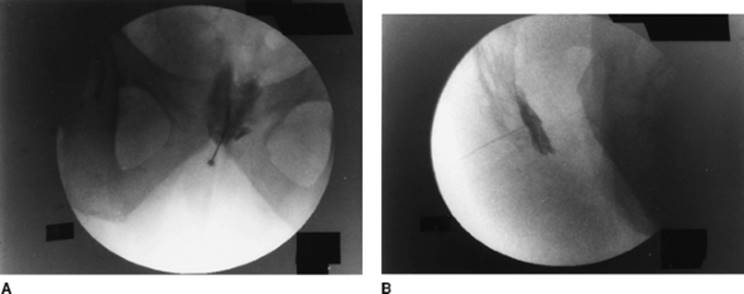

Approach and Technique: The lumbosacral region is prepared and draped using sterile techniques. The sacrococcygeal junction and the tip of the coccyx are located using fluoroscopy. The midline is identified and a skin wheal using a 25-gauge needle with 1% lidocaine is performed. The spinal needle is advanced perpendicular to the skin at the sacrococcygeal junction, and its tip is placed anterior to the sacrococcygeal junction using fluoroscopy, confirming appropriate position using anteroposterior and lateral views. After careful aspirate for blood, air, or feces, and after negative aspiration, the radiocontrast dye is injected to confirm the spread of contrast medium just anterior to the sacrococcygeal junction. This is then followed with injection of the local anesthetic mixture/phenol. Figure 63-8 presents the anteroposterior (A) and lateral view (B).

Figure 63-8. Anteroposterior (A) and lateral (B) view of ganglion impar block.